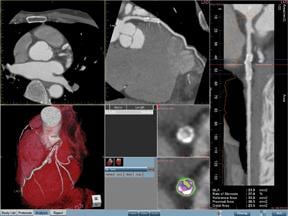

Aquarius iNtuition by TeraRecon offers a range of options to deliver an advanced, procedural workstation configuration for the 3D technologist, a powerful reading / browsing station for the diagnosing physician and a fast, simple 3D review tool.

As the latest generations of magnetic resonance imaging systems (MRI), computer tomography systems (CT) and 3D ultrasound render volumetric images with high resolution and detailed anatomical information, enabling clinicians to better depict anatomies. Medical anomalies are greatly improved as the imaging industry leverages the potential that can be reached using new mathematics and algorithms for image enhancement, projections and rendering. In addition, the use of high-speed computation technology in multiple core computers and graphics processors makes advanced medical images instantly available.

Ultrafast processing capabilities reduce the time needed to review images, which is crucial when reviewing 3D images. For example, in cardiac applications, real-time ultrasound volumetric imaging has been challenged. However, using modern high-performance computing platforms (HPC), such as graphical processing units (GPUs), digital signal processors (DSPs), FPGA/ASICs, or multiple core computers, new diagnostic functionality can be achieved. A modern GPU typically processes an image 256-pixels wide in real-time at a rate up to 20 images per second. This speed enables real-time speckle and noise reduction, as well as image quality improvements. Here, the new platform empowers clinicians to make online and real-time diagnosis of the beating heart. In addition, organs and deep embedded structures can be seen in their context, revealing actual geographic position and orientation. These substantial clinical benefits deliver numerous diagnostic opportunities, as well as dose reduction possibilities.

Visualization of the heart in 3D is already possible and provides the physician with a tool to review its anatomical structure, identifying congenital heart anomalies or other changes. However, depicting the beating heart and performing real-time estimations to reveal information related to wall motion or other clinical information requires tremendous computational power, such as that available in multicore CPUs and other HPC platforms.